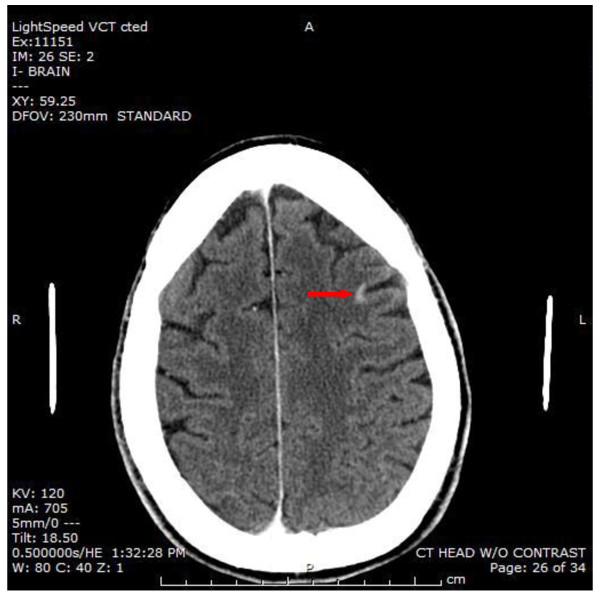

Extension of primary lung tumors into the left atrium via pulmonary veins is a well-documented phenomenon. Peripheral arterial embolism and cerebral embolism originating from a primary lung neoplasm are rare events. We report a case of simultaneous acute bilateral lower limb ischemia, bilateral renal infarction, splenic infarction and cerebral infarction as a result of multiple emboli originating from primary lung malignancy invasion of the left atrium. An emergent embolectomy revealed pathologic features of the extracted thrombus that were identical to the pulmonary neoplasm.

原发性肺肿瘤经肺静脉延伸至左心房是一种有充分文献记载的现象。源自原发性肺肿瘤的外周动脉栓塞和脑栓塞是罕见事件。我们报告一例因原发性肺恶性肿瘤侵犯左心房导致多发栓子形成,进而出现同时性急性双侧下肢缺血、双侧肾梗死、脾梗死和脑梗死的病例。急诊栓子切除术显示取出的血栓病理特征与肺肿瘤相同。